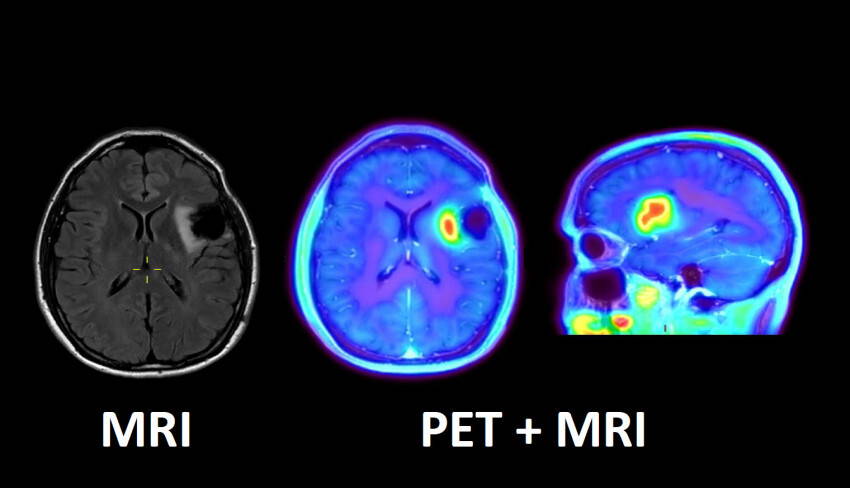

Het Maastricht UMC+ beschikt voortaan over een techniek om hersentumoren optimaal in beeld te brengen in één onderzoek. De techniek maakt gebruik van een radioactieve stof (FET) in combinatie met een PET/MRI-scan. Van deze scanner zijn er maar twee in Nederland. De gecombineerde methode is volgens het umc nauwkeuriger én patiëntvriendelijker, want er is maar één scan nodig. Limburgse patiënt hoeven bovendien niet meer voor het betreffende onderzoek naar het buitenland gestuurd te worden.

FET (Fluor-Ethyl-Tyrosine) is een aminozuur en wordt opgenomen in gebieden waar veel eiwitten worden aangemaakt. Dat is bijvoorbeeld het geval bij bepaalde kwaadaardige hersentumoren zoals glioblastomen. Met een PET/MRI-scanner (Positron Emissie Tomografie en Magnetic Resonance Imaging gecombineerd) kan de opname van FET in de hersentumor exact ‘gemeten’ en in beeld gebracht worden. Dat is bijvoorbeeld van belang om te bepalen wat de beste plek is om een neurochirurgisch biopt te nemen.

Ook kan beeldvorming met deze nieuwe methode helpen om de effecten van bestraling te onderscheiden van groei van de tumor. Het doel van bestraling is dat de tumor slinkt, maar het omliggende weefsel kan ook op de bestraling reageren. Met een MRI is het niet altijd goed mogelijk om het verschil te zien tussen de verandering van omliggend weefsel en eventuele groei van de tumor. De nieuwe FET-PET/MRI wordt met name aangevraagd voor patiënten bij wie twijfel is over het effect van de behandeling.

De nieuwe manier van beeldvorming van een hersentumor wordt zoveel mogelijk uitgevoerd in de hybride PET/MRI-scanner van het Maastricht UMC+. Deze scanner combineert twee beeldvormingstechnieken in één scanner. Met PET (Positron Emissie Tomografie) kunnen met een radioactieve stof bepaalde processen van organen en weefsels in beeld worden gebracht. Bij MRI (Magnetic Resonance Imaging) worden door een combinatie van sterke magnetische velden en radiogolven beelden gemaakt.